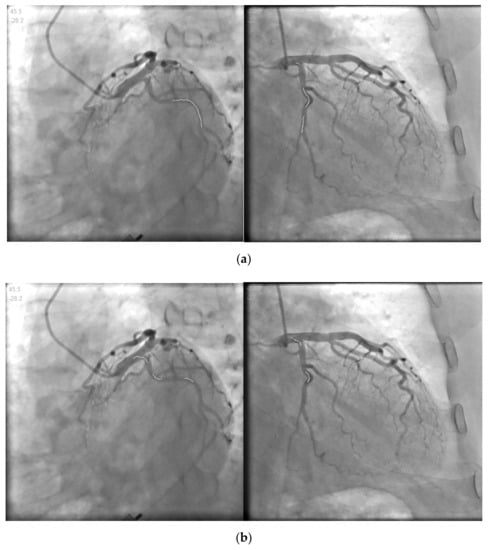

As shown in Table 1, there are three types of clinical data for pole-matching problems in the table. We used these data to reconstruct 3D points. As shown in Figure 7, the solid white line in the blood vessel is the centerline of the blood vessel to be reconstructed.

Figure 7.

Clinical contrast images for reconstruction. (a,b) are Data.1; (c,d) are Data.2; (e,f) are Data.3.